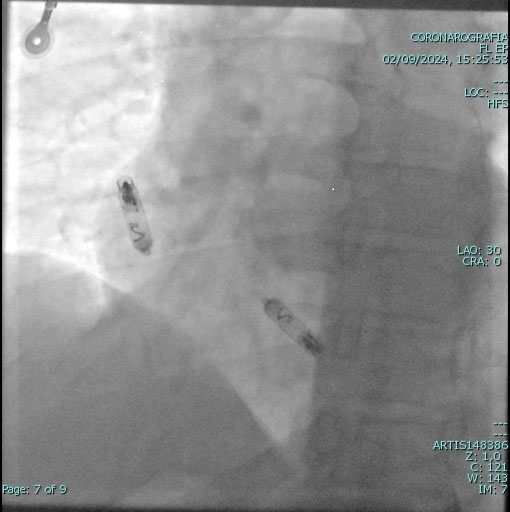

È una procedura che permette di eliminare definitivamente i substrati anatomici, responsabili di molte aritmie cardiache, col semplice utilizzo del calore (la temperatura non supera i 56-58 gradi), portato all'interno del cuore sulla punta di appositi cateteri. Va ricordato che la procedura è del tutto indolore, in quanto all'interno del cuore non esistono terminazioni nervose che trasportino la sensazione dolorosa (si sente la stessa sensazione, ossia nulla, che si percepisce stirando i capelli con un ferro caldo!). Dopo la procedura non sarà più necessario alcun farmaco per controllare l'aritmia. Prima di sottoporre un paziente all'ablazione, viene eseguita una serie di esami clinici, per garantire la massima sicurezza e tranquillità (esami del sangue, elettrocardiogramma,ecocardiogramma, ecc.).

L' ablazione trans-catetere viene eseguita in anestesia locale (come quella che usa il dentista). Attraverso una vena e/o un'arteria della coscia, che passa in regione inguinale (se necessario viene a volte utilizzata anche una vena del braccio o una vena sotto la clavicola sinistra), vengono introdotti dei fili elettrici (i cosiddetti “elettro-cateteri”) e guidati, sotto controllo radiologico, fino all'interno delle cavità cardiache; tale manovra è assolutamente indolore e non viene avvertita dal paziente.

Una volta posizionati nelle cavità cardiache, i cateteri sono collegati a particolari apparecchiature che registrano l'attività elettrica all'interno del cuore; tutto ciò è completamente indolore, come un qualsiasi elettrocardiogramma.

Elettrofisiologia cardiologia Vallo della Lucania Elettrofisiologia cardiologia Vallo della Lucania

Durante l'ablazione è necessario stimolare il cuore con piccolissimi impulsi elettrici emessi dai cateteri (non percepiti dal paziente), in modo da poter provocare l'aritmia in esame e identificare la zona da cui ha origine. Con opportuni stimoli elettrici l'aritmia può essere interrotta dall'operatore. Una volta identificato il punto di origine dell'aritmia, si procede all'ablazione propriamente detta: mediante uno dei cateteri, già presenti all'interno delle cavità cardiache, si trasmette una particolare corrente elettrica, chiamata “radiofrequenza”, che scalda la punta del catetere stesso (la temperatura non va mai oltre i 60 gradi); il calore determina la coagulazione del punto responsabile dell'aritmia, che viene, in tal modo, soppresso.